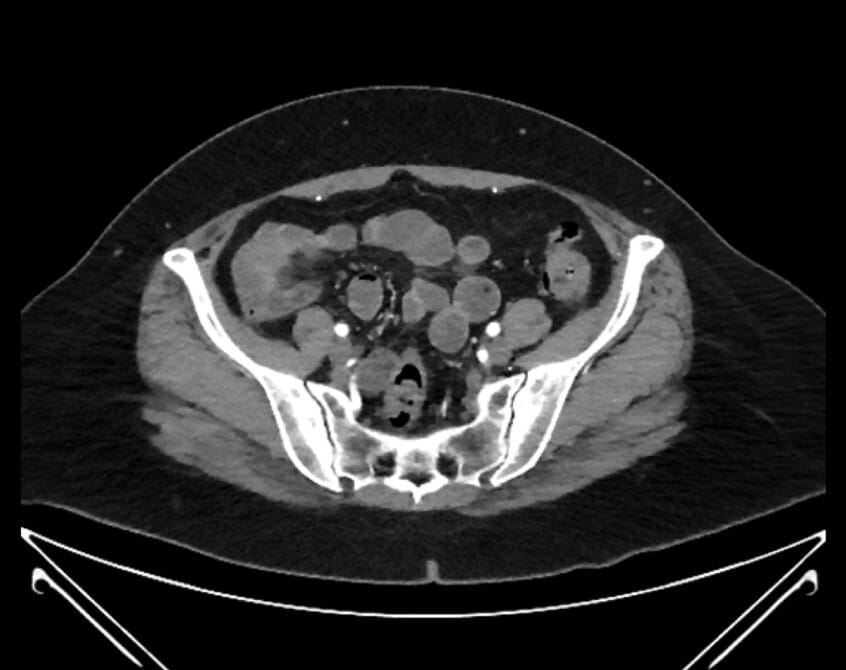

61. external iliac artery

62. iliolumbar artery

63. internal iliac artery

64. superior rectal artery

65. posterior division of internal iliac artery

66. anterior division of internal iliac artery

67. superior gluteal artery

68. inferior epigastric artery

69. deep circumflex iliac artery